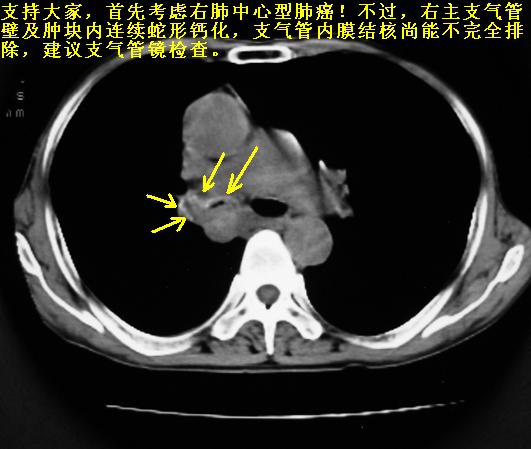

以下是引用同在2007-1-27 14:13:00的发言:[br]支持右侧中央型肺癌伴阻塞性病变.

以下是引用zjzjr在2007-1-27 16:56:00的发言:[br]支持右肺中心型肺癌伴阻塞性肺炎.